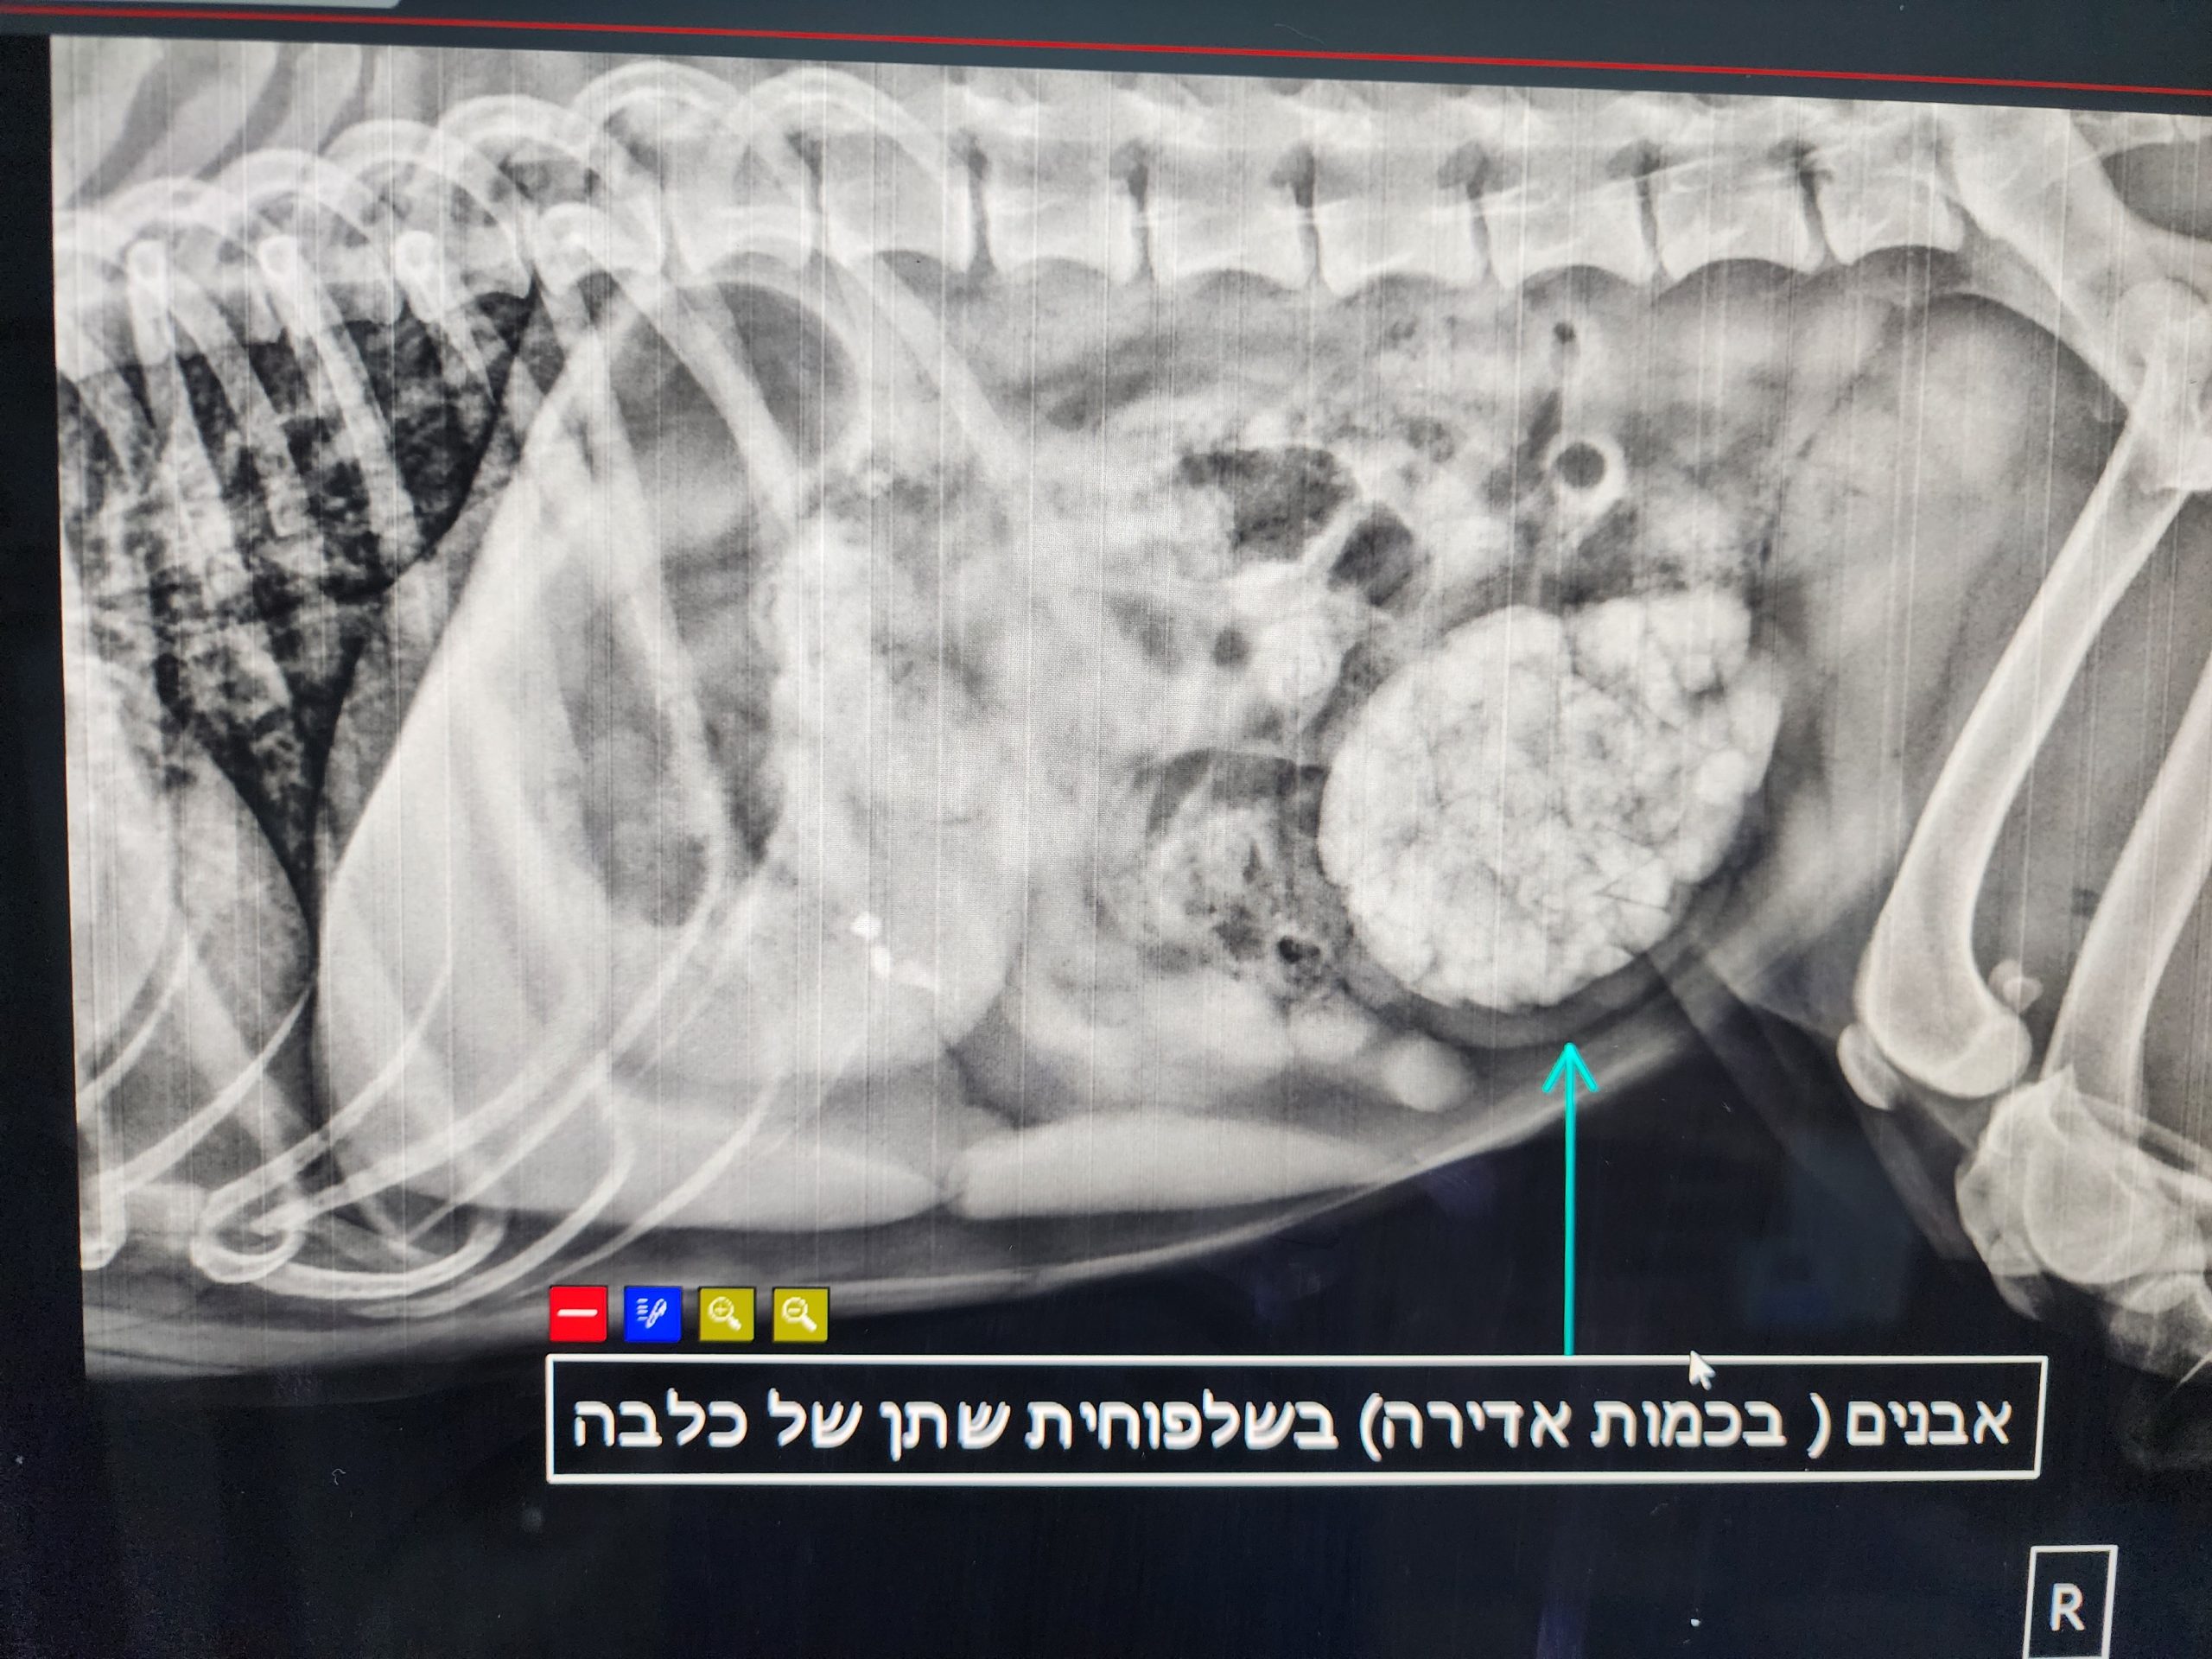

רנטגן 5

רנטגן 6

רנטגן 7